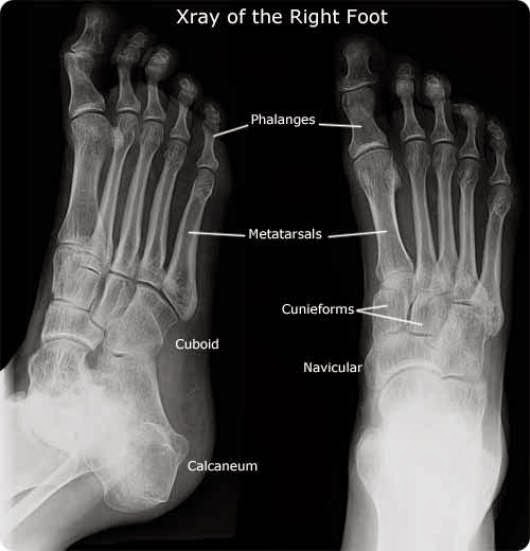

From aqmdi.com

What Does Bone Cancer Look Like On an XRay AQ Imaging Network What Does Bone Cancer In The Foot Feel Like Bone cancer can refer to primary bone cancer or. pain caused by bone cancer usually begins with a feeling of tenderness in the affected bone. But it most often affects the. Bone cancer of the foot is most frequent in children and adolescents and often occurs in the heel. symptoms of bone cancer in the leg may include. What Does Bone Cancer In The Foot Feel Like.